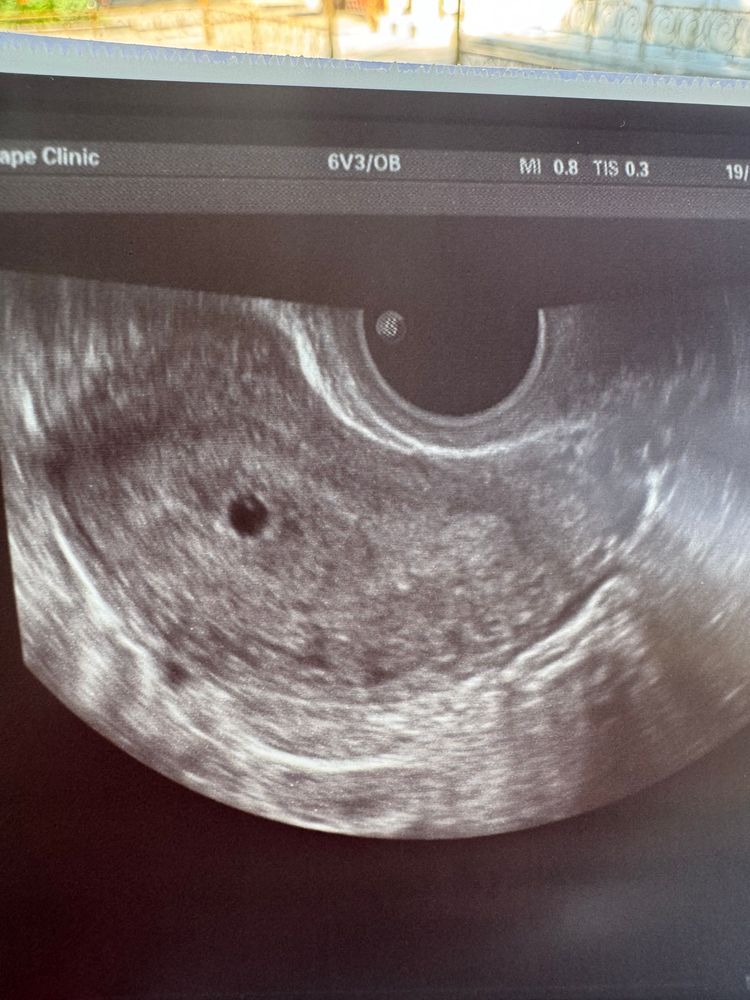

Вчера увидели ПЯ ✨

УЗИ, КТГ, доплерСегодня 5.4 недели, увидели ПЯ, говорит врач что есть что то похожее на ЖМ и эмбрион, но еще не может написать в заключении что это оно, так как рано

девочки, сейчас такая смотрю на фото, это ж белая капелька внутри пя, может вообще быть оно?😁

Это желточный мешочек)